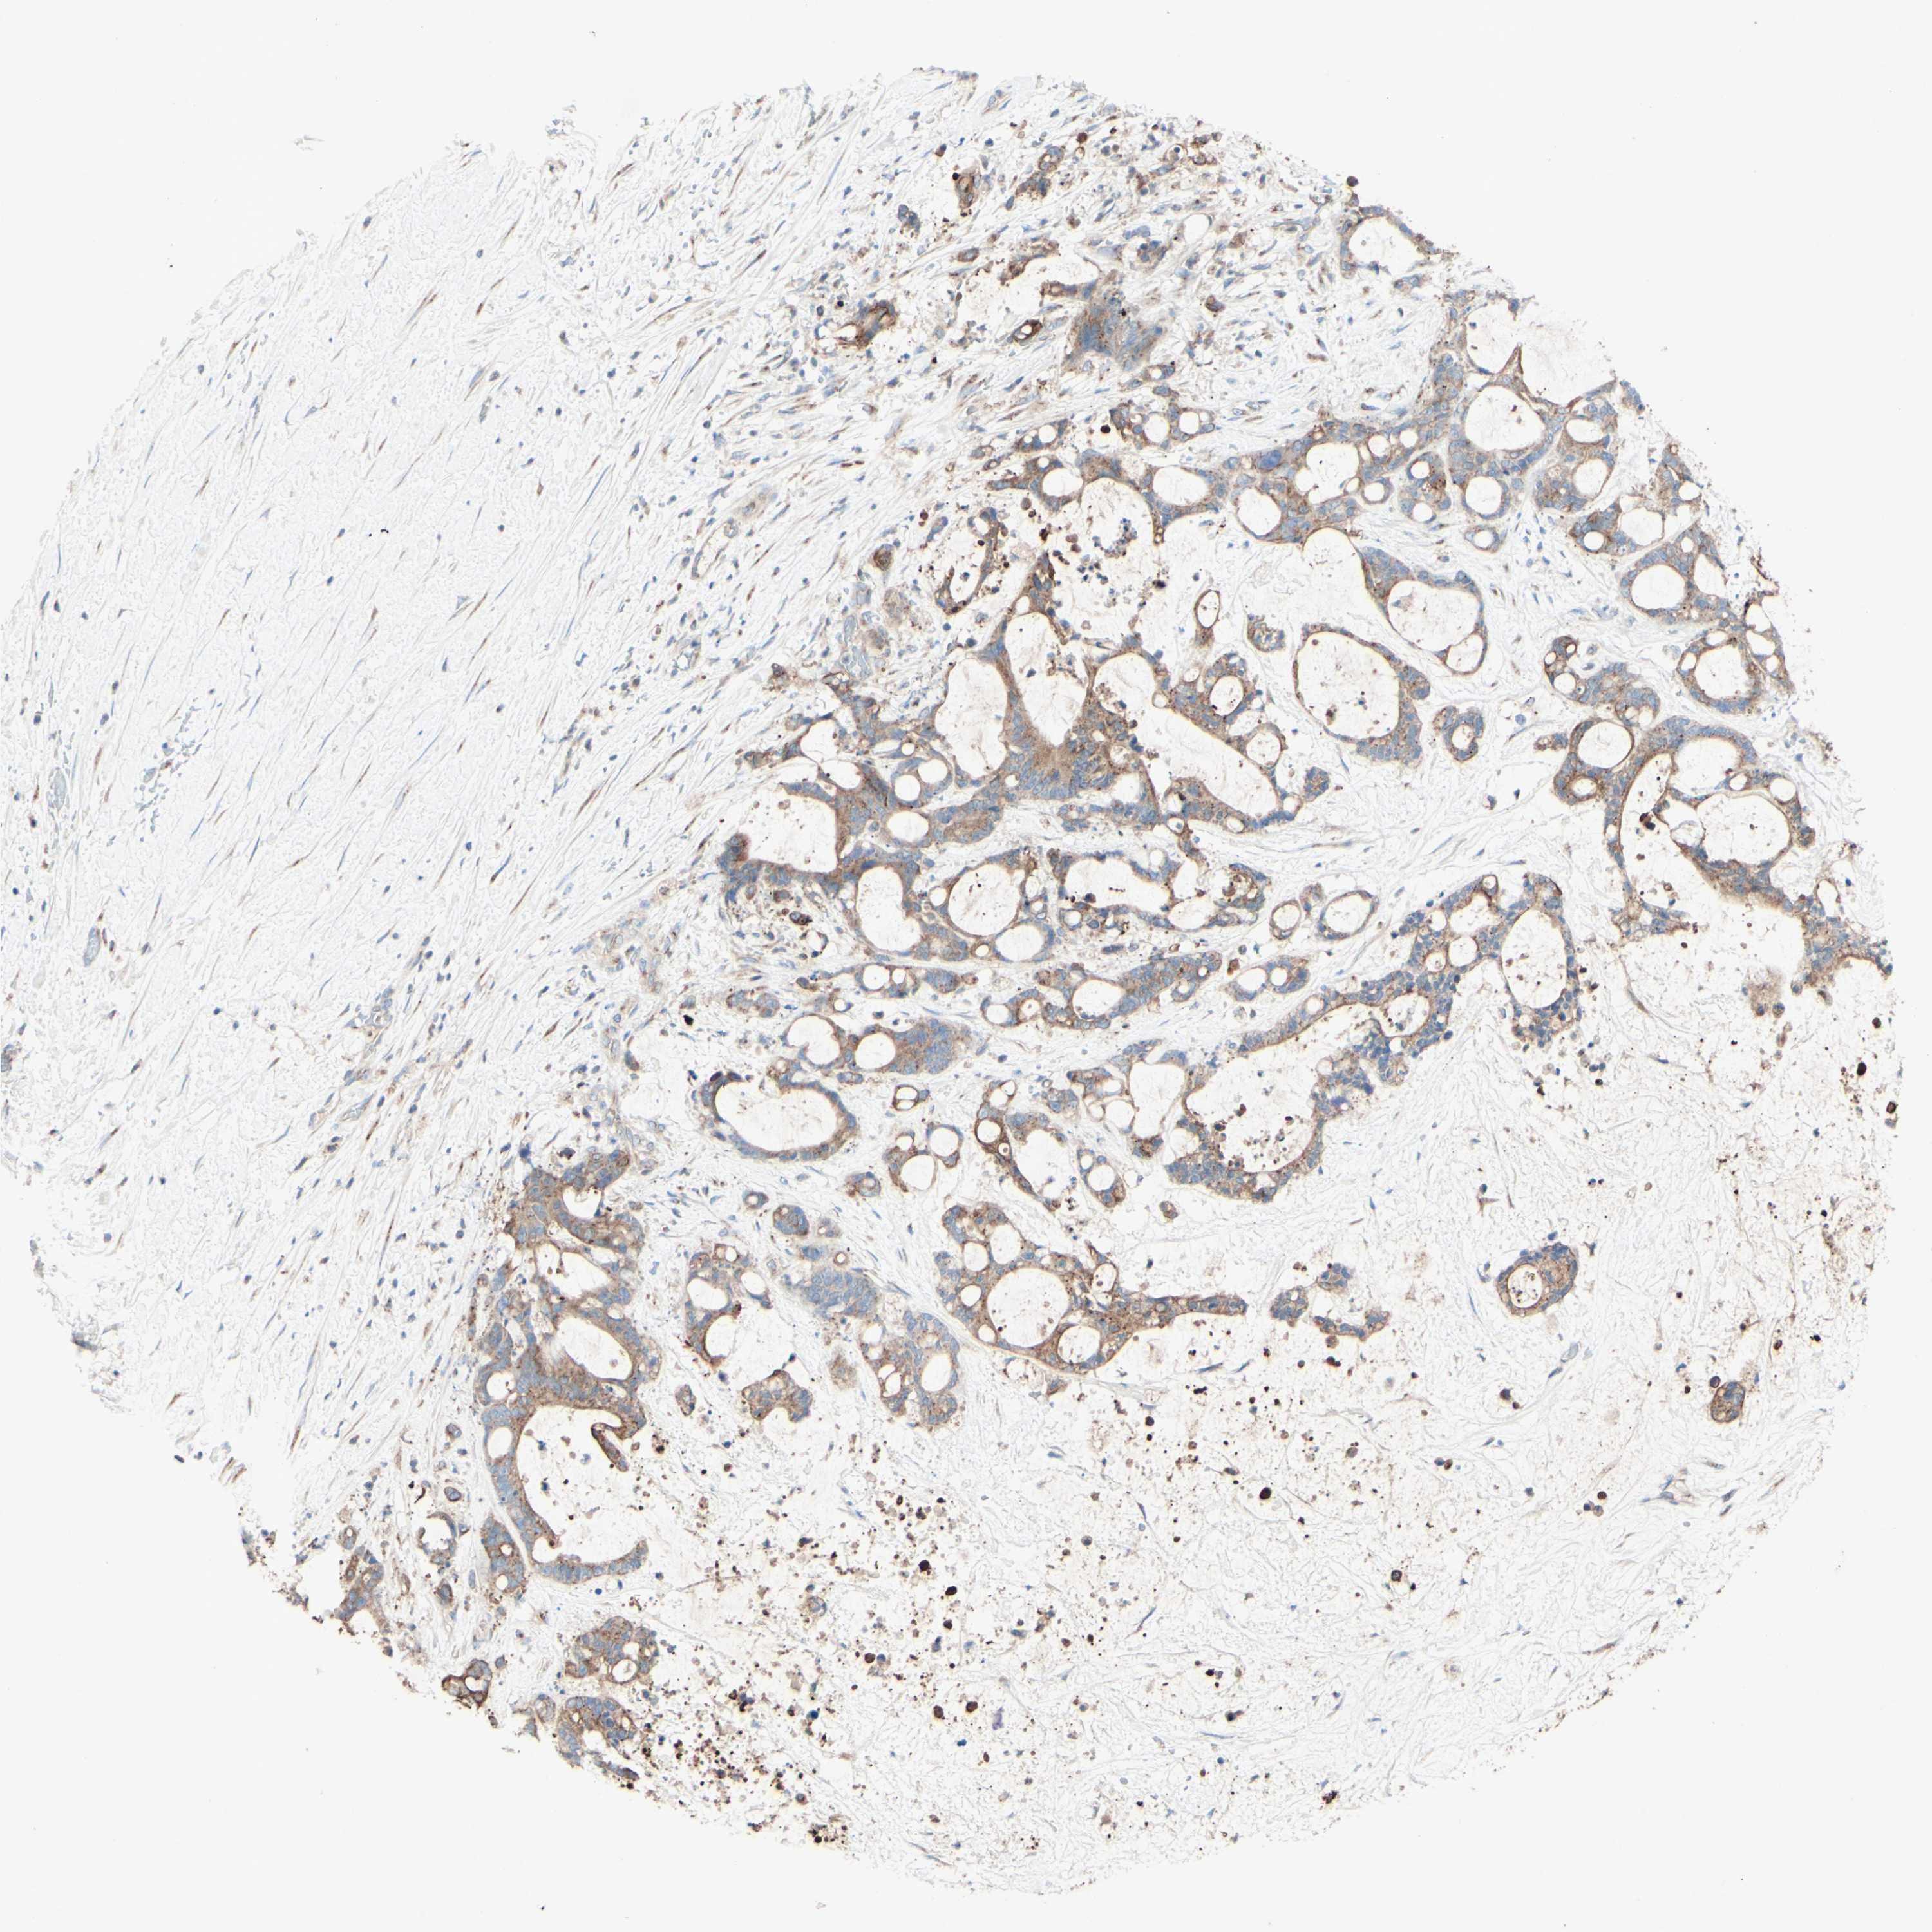

LIVER CANCER - Protein expressioni

A mouse-over function shows sample information and annotation data. Click on an image to view it in a full screen mode. Samples can be filtered based on level of antibody staining by selecting one or several of the following categories: high, medium, low and not detected. The assay and annotation is described here.

Antibody stainingi

Antibody staining in the annotated cell types in the current human tissue is reported as not detected, low, medium, or high, based on conventional immunohistochemistry profiling in selected tissues. This score is based on the combination of the staining intensity and fraction of stained cells.

Each image is clickable and will lead to virtual microscopy that enables deeper exploration of all samples and also displays staining intensity scores, fraction scores and subcellular localization as well as patient and tissue information for each sample.

Antibody HPA010008

Antibody HPA010665

Staining

High

Medium

Low

Not detected

Intensity

Strong

Moderate

Weak

Negative

Quantity

>75%

75%-25%

<25%

None

Location

Nuclear

Cytoplasmic/membranous

Cytoplasmic/membranous,nuclear

Cholangiocarcinoma

Carcinoma, Hepatocellular, NOS